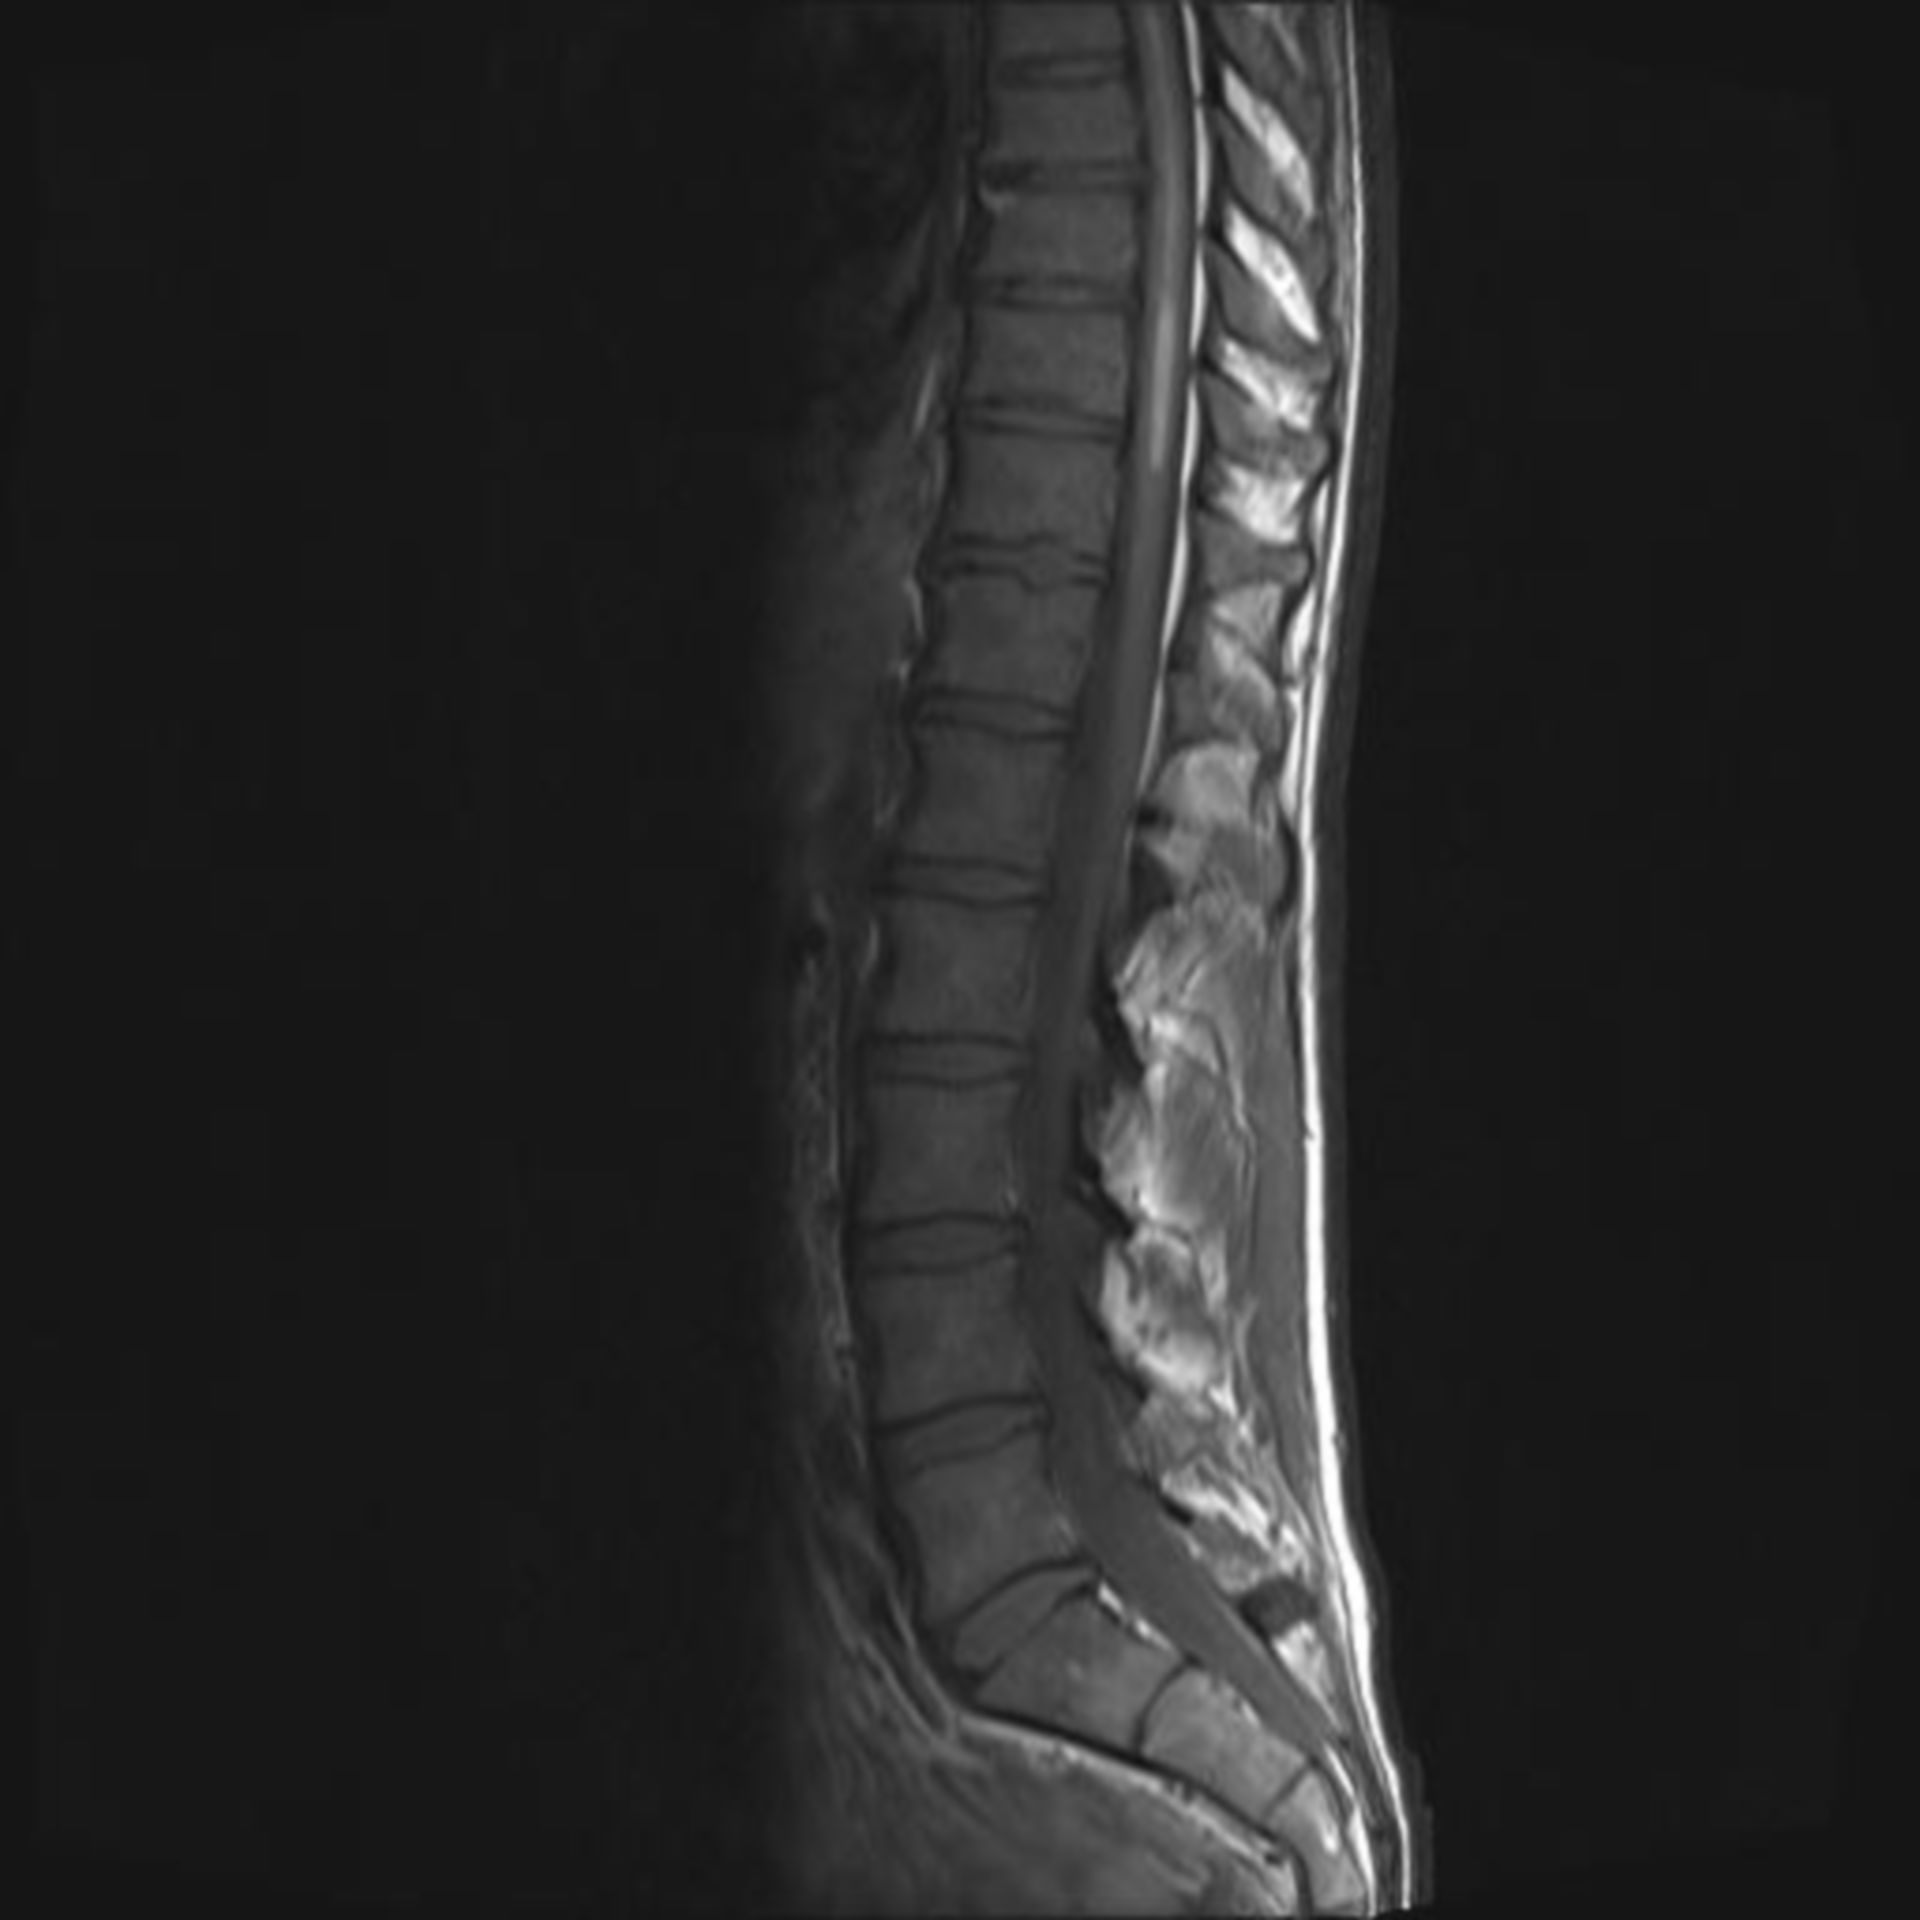

MRT HWS 1 – DocCheck

Abbildung 1: (a) MRT der HWS in T2-Gewichtung, sagittale… | Download …

Abbildung 4a-d: HWS – MRT

Mrt Hws – Mrt Hws Bws T2 Gewichtet Sagittal : Maybe you would like to …

MRT Aufnahme der HWS Foto & Bild | industrie und technik, technik …

MRT HWS (Halswirbelsäule): Gründe, Ablauf, Dauer | praktischArzt

MRT BWS 2 – DocCheck